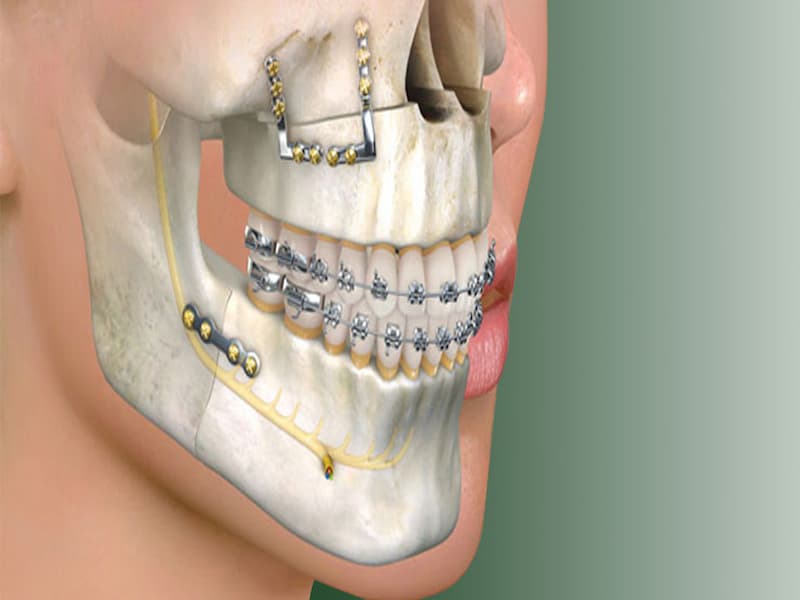

اصولا دندان پزشکان برای انجام ایمپلنت قبل از هر کاری سطح لثه را جراحی می کنند تا بتوانند ایمپلنت را در جای مناسب قرار دهند.

ایمپلنت از جنس فلز بوده و ظاهری همانند پیچ را دارا می باشد که امروزه به اسم فیکسچر نیز در بین مردم شناخته می شود.

به طور کل محل جوش خوردن آن در فک بالا می باشد که با توجه به جای خاص آن می توانیم بگوییم پایه ای برای دندان های کشیده شده و از دست رفته در نظر گرفته می شود.

اباتمنت نیز که بر روی ایمپلنت فک بالا قرار می گیرد و جایگزینی برای تاج دندان بوده که نقش جویدن غذا را می تواند به خوبی تمام انجام دهد.